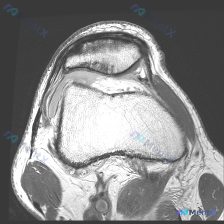

刚整理完一份膝关节MRI读片病例,核心问题是发现软骨异常,把完整的分析思路分享给大家。 一、影像基本信息 本次影像为膝关节冠状位T2加权脂肪抑制序列MRI,已经清晰显示膝关节主要结构,脂肪抑制序列很好突出了水肿、积液等异常高信号。 二、已明确的影像学发现 1. 半月板:内侧半月板体部形态完整,内部可...

刚整理完一份很有代表性的膝关节MRI读片病例,分享一下思路,很多人容易踩锚定效应的坑。 一、基本病例影像信息 这是一份膝关节MRI-T2序列冠状位的影像学检查,我们按解剖系统梳理发现: 1. 骨骼关节:股骨远端、胫骨近端显示清晰,股骨外侧髁骨皮质下方可见明显信号异常,关节间隙双侧都存在,关节对位尚可...

看到这个膝关节MRI的病例,整理一下完整的分析思路,这个病例特别容易只关注半月板漏了更重要的问题,分享出来大家一起讨论。 病例基本影像信息 这是一张膝关节MRI冠状位T2加权像,核心发现整理如下: 1. 骨骼结构:股骨远端、胫骨近端骨皮质连续,胫骨外侧平台可见片状明显高信号,提示急性骨髓水肿/骨挫伤...

整理了一份膝关节MRI读片病例,核心问题是半月板异常,分享一下完整的分析思路,大家一起讨论。 病例影像基础信息 这是膝关节MRI冠状位T2加权脂肪抑制序列影像,我们来看具体的征象: 1. 骨骼结构:股骨远端、胫骨近端骨皮质完整,无骨折或骨质破坏,骨髓信号无异常高信号,没有明显骨髓水肿 2. 半月板情...